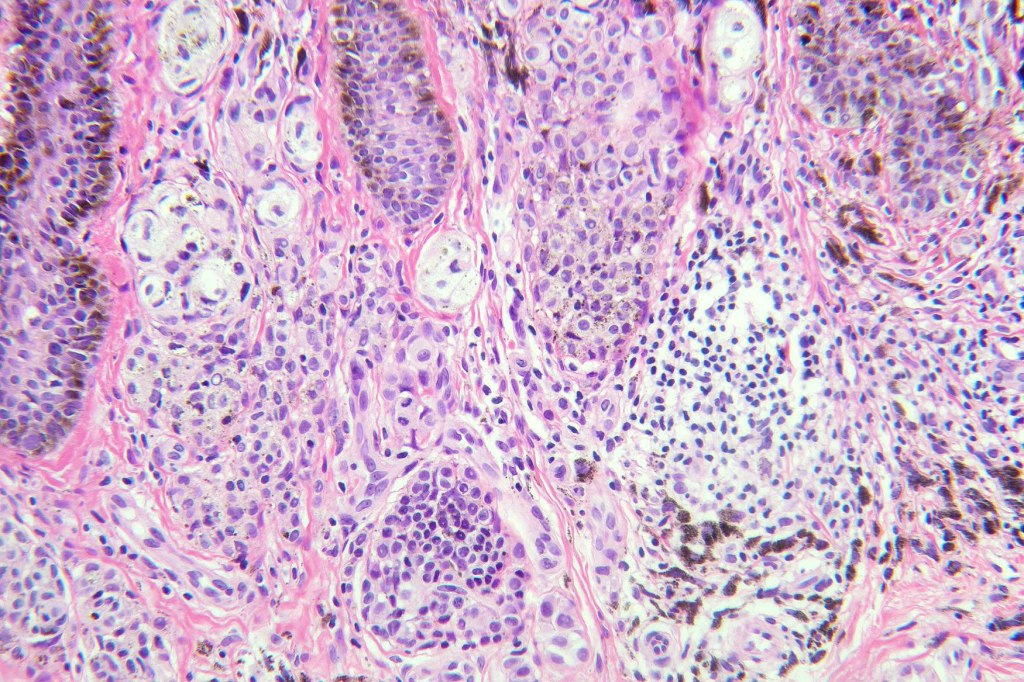

•May affect the tumor in part or whole

•Enlarged cells with copious eosinophilic, foamy or clear cytoplasm (some authors include melanoma with clear cell change in the same category)

•Variable pigmentation

•Nuclei vesicular or hyperchromatic

•Pleomorphism is not generally marked and indeed can be very subtle

•Variable mitotic activity

•DPAS granules